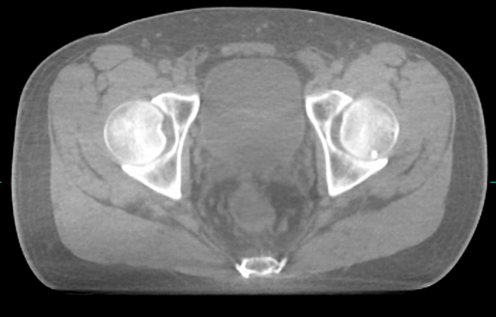

Prostate treatment in 2 fractions (HERMES trial)1